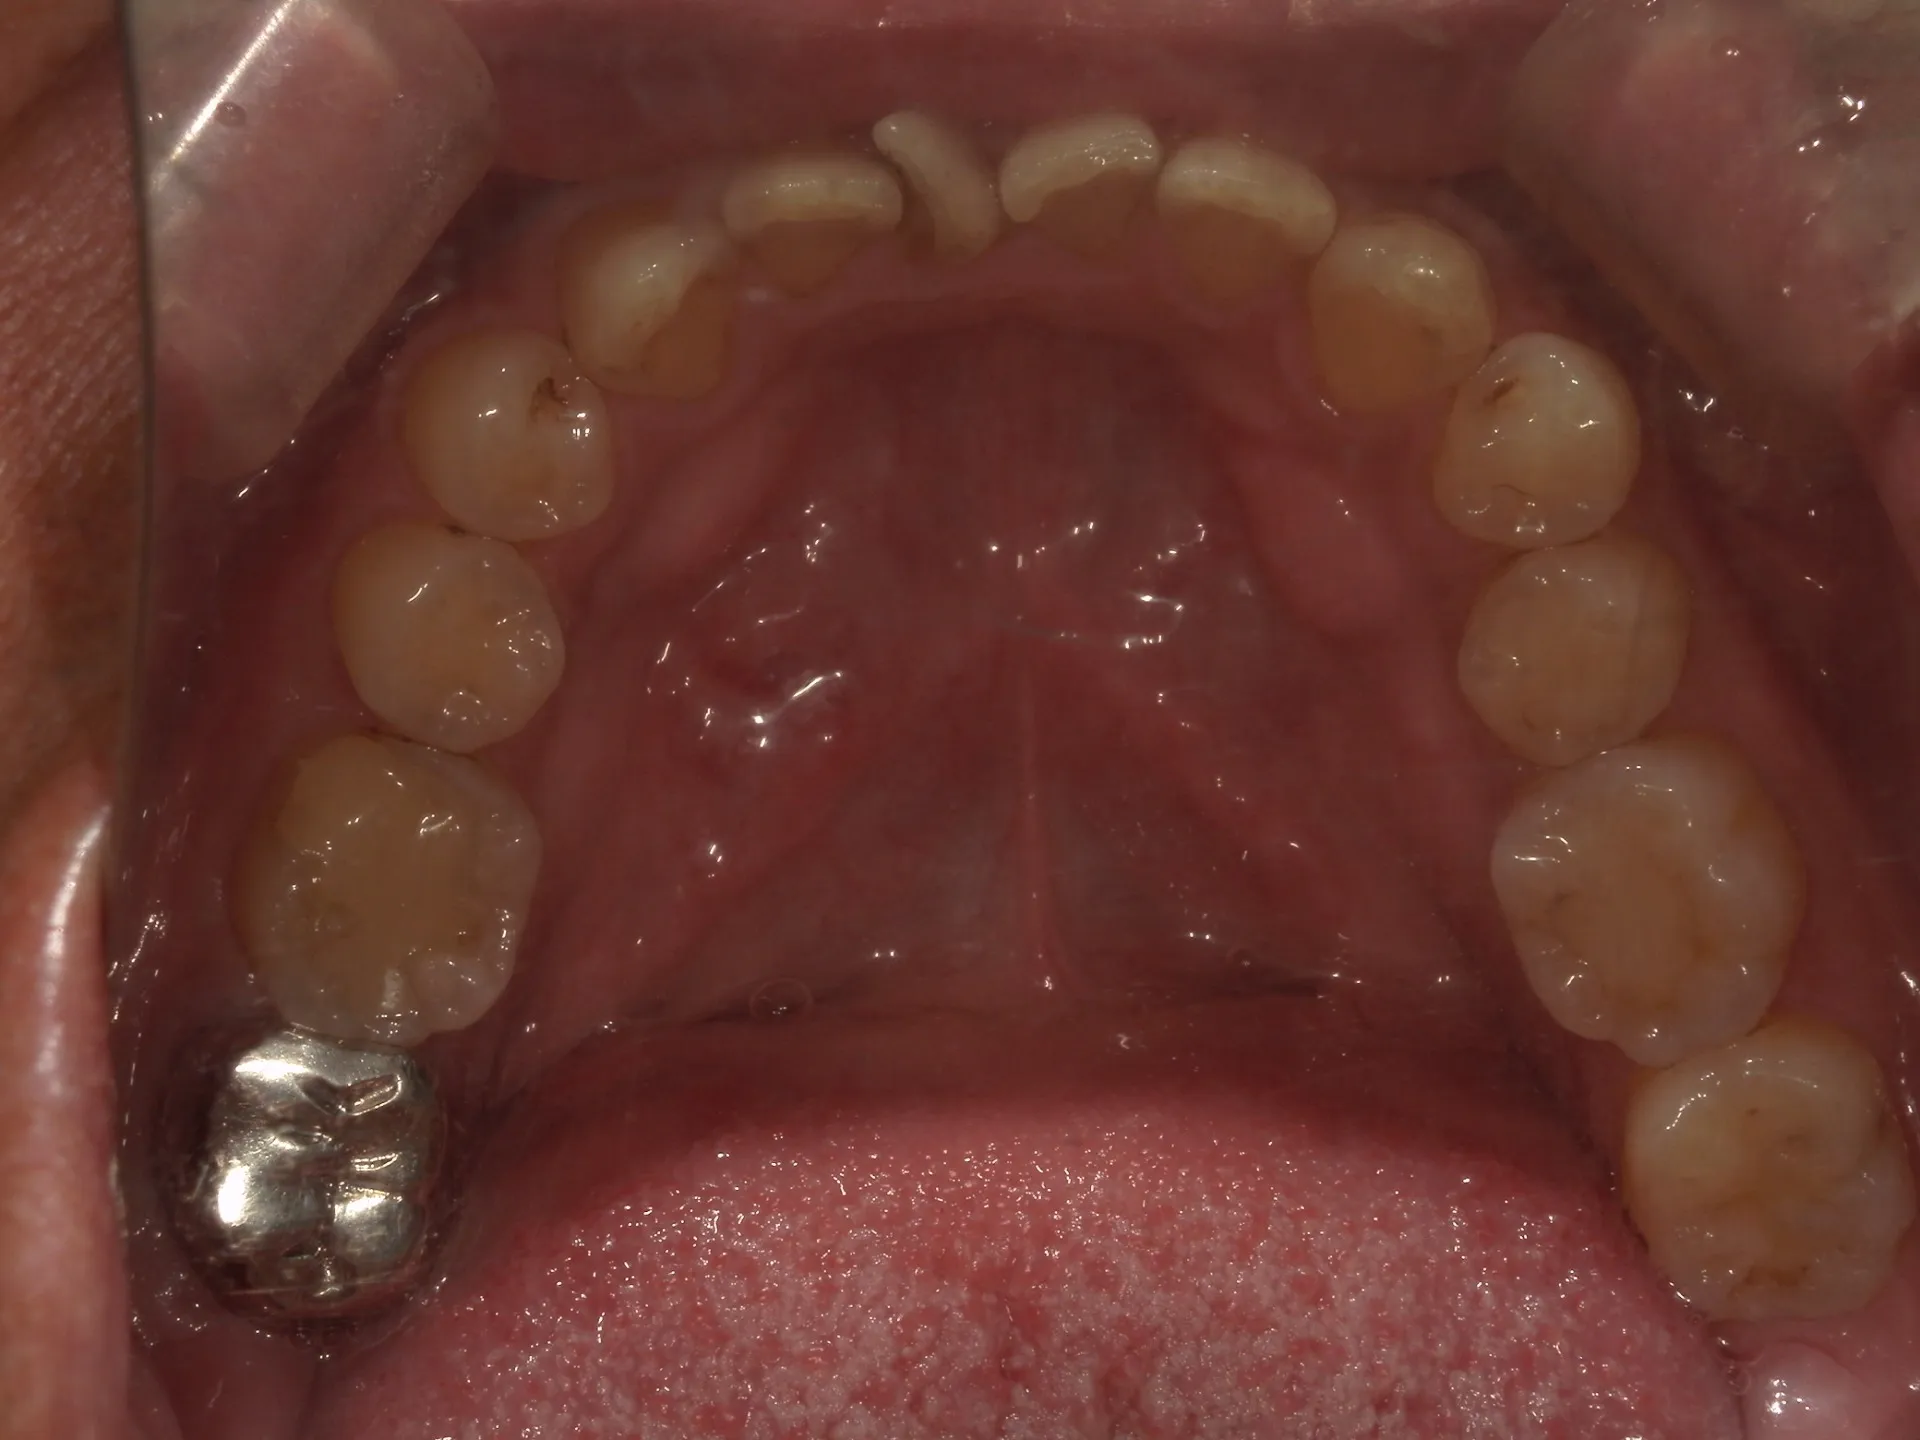

保険の歯のクリーニングと自費のPMTCでは何が違うのでしょうか??

歯の「保険の掃除」と「自費のPMTC」には目的や範囲、使える機材・時間に違いがあります。